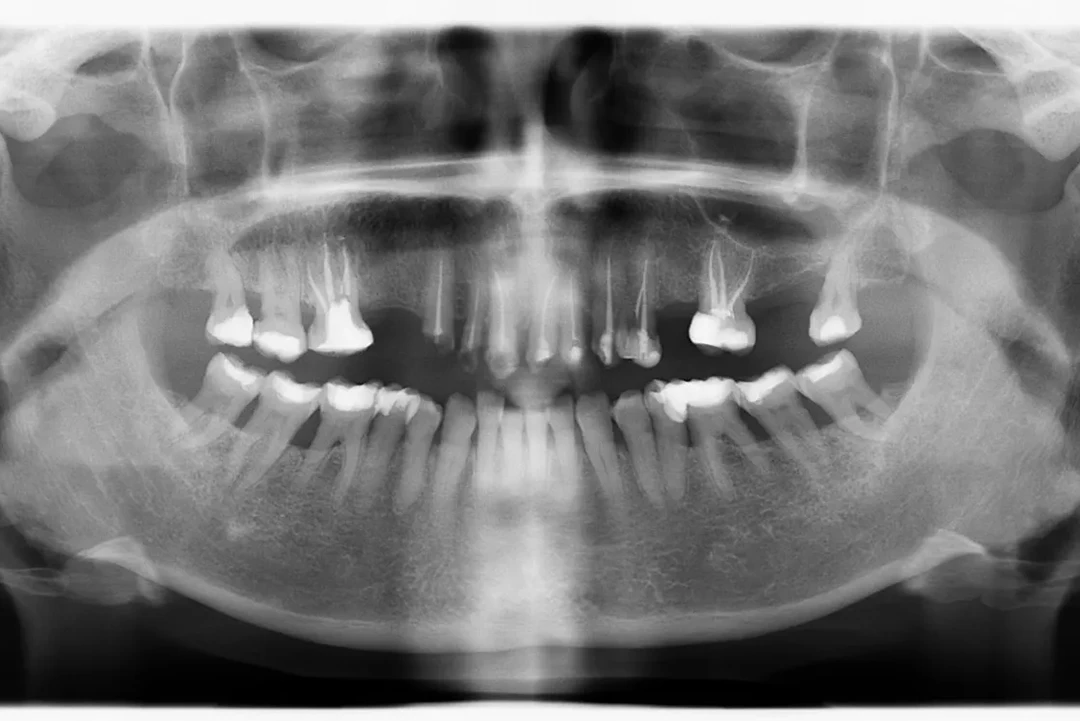

De 61 años nos visita con dientes dañados por caries y una prótesis antigua que ya no podía utilizar. Gracias a la planificación digital y la cirugía guiada, realizamos las extracciones y colocamos implantes con una prótesis fija el mismo día. Recuperó su sonrisa y la confianza de inmediato.